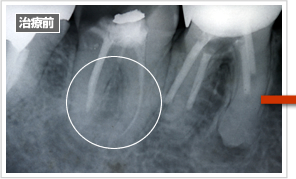

以下の症例でも根の先の溶けた歯が治療後には再生しています。

根管の治療前 根管の治療後